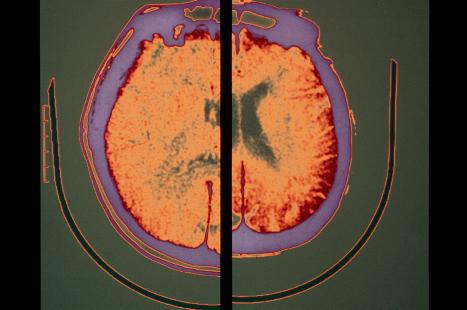

L’immunothérapie administrée à un stade précoce de la maladie pourrait en modifier l’évolution, permettant un ralentissement du déclin cognitif. Plusieurs essais sont en cours en France et aux États-Unis. Page 3

Immunothérapie précoce dans la maladie d’Alzheimer

Crédit photo : PHANIE